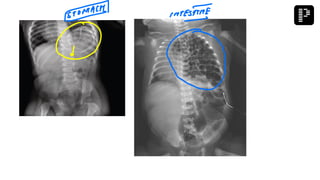

a. Adhesive small bowel obstruction

Q. A multipara patient was brought to the emergency with signs and symptoms of small bowel

obstruction. After resuscitation, X-ray was performed and the findings are given below.

What is the most probable diagnosis?